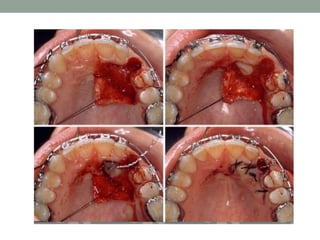

• SURGICAL EXPOSURE:

• Indicated when tooth does not erupt spontaneously after

creating space in the arch.

• Attempted 6 months after the root formation.

• Flap designs should preserve the band of attached

gingiva and should guide tooth to erupt through its natural

path of eruption.

• PALATAL IMPACTION OF MAXILLARY CANINE:

CLOSED

ERUPTION

Crown is surgically exposed, an

attachment is bonded during the

exposure, flap is sutured back,

leaving a twisted ligature wire

passing through the mucosa to

apply orthodontic traction.

OPEN WINDOW

TECHNIQUE

A flap is raised, bone covering

crown is removed, small window

or fenestration is made,

orthodontic attachment is bonded

and flap is sutured into place.